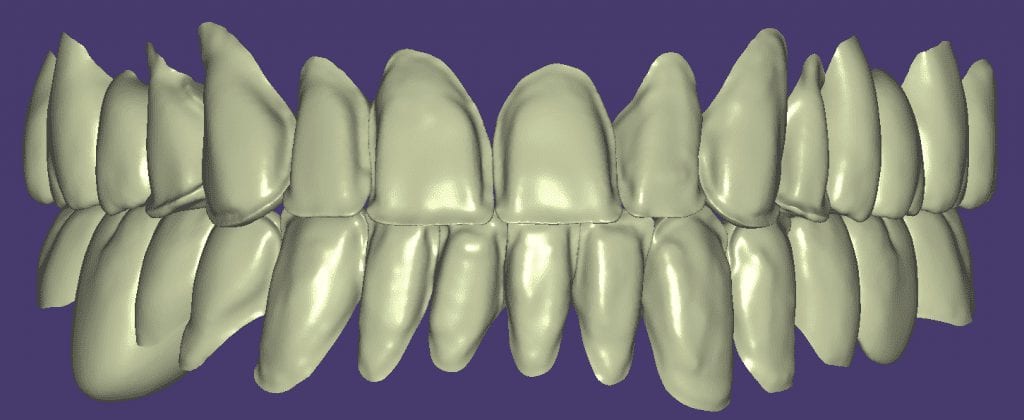

Over the course of a few appointments, the vertical dimension was reduced and the temporaries were adjusted to the patient’s desires. The new upper and lower arch were captured with the Medit i500 and the jaws were related to each other.

This was then imported into exocad where the prepped arches from a few weeks prior were force matched to the new bite

After the upper jaw was related to the temps, the same was done with the lower arch. Great care was taken to make sure the arches were properly related to each other throughout the process